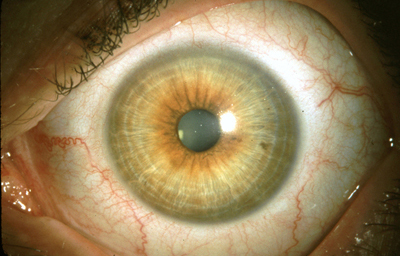

En los humanos y en la mayoría de los mamíferos y pájaros, el Iris es una estructura anular en el ojo, responsable de controlar el diámetro y tamaño de la Pupila y controlar así la cantidad de luz que penetra al Ojo. En términos de la Optica, el Iris es el diafragma y la pupila su apertura. El color del ojo se define según el color del Iris.

Separa la cámara Anterior de la cámara Posterior en el Ojo, y esta situado por delante del Cristalino; se compone de 3 capas: la hoja Anterior del Iris (membrana pupilar) cuya atrofia parcial genera las criptas de Fuch´s, el Estroma, capa fibrovascular y pigmentada, no tiene epitelio y su origen es mesodérmico; la Posterior debajo del estroma, es una capa de células epiteliales pigmentadas con un grosor de 2 células, conocida como el Epitelio pigmentario del Iris cuyo origen viene del neuroectodermo.

En la cara Anterior esta el pigmento que le da el color al Iris y dependiendo del grado de reabsorción u atrofia de esa capa anterior se pueden observar:

Las Criptas de Fuchs: que son pequeñas aberturas alrededor del collarete, producto de la atrofia o reabsorción de la hoja anterior del iris, que le permiten al estroma y a los tejidos mas profundos estar en contacto con el humor acuoso.

Cuando el Iris no tiene criptas, se considera que la reabsorción u atrofia de la hoja anterior (memb. pupilar) se detuvo en el circulo menor.